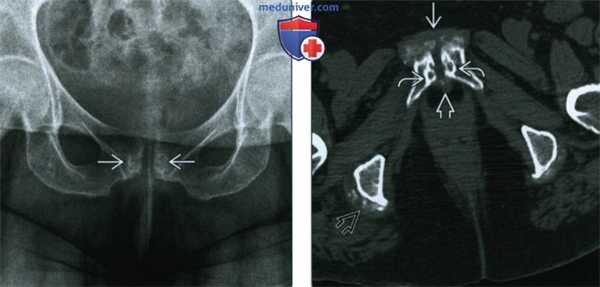

(Слева) КТ, аксиальный срез: у этого игрока регби 21 года определяется склероз, неровность и эрозии вдоль ЛС, что указывает на хронический ОЛК. КТ позволяет выявить хронические признаки ОЛК, но обычно не используется для постановки диагноза. Обратите внимание на пролиферативные изменения кости при хронических разрывах приводящих мышц.

(Справа) КТ, 3D реконструкция поверхности: у этого же пациента подтверждена неровность ЛС, что указывает на длительный ОЛК. (Слева) При рентгенографии в передне-задней проекции у регбиста 20 лет определяется асимметричный склероз кости и эрозии при хроническом ОЛК. Значительный склероз и эрозии свидетельствуют о длительном течении. Признаки острого ОЛК в первую очередь включают в себя отек костного мозга, который не визуализируется при рентгенографии.

(Слева) При рентгенографии в передне-задней проекции у игрока в американский футбол с постоянной двусторонней болью в паху определяется небольшой субхондральный склероз и ранняя резорбция в области ЛСВ, которые иногда могут остаться незамеченными.

(Справа) Сцинтиграфия костей с МДФ, меченной Тс-99, в передне-задней проекции: у этот же пациента определяется интенсивное поглощение радиометки вокруг ЛС при картине, схожей с субхондральным отеком костного мозга, который визуализируется на МРТ при остром ОЛК. ОЛК часто не визуализируется или слабо выражен при рентгенографии. (Слева) МРТ Т2ВИ, режим подавления сигнала от жира, косой аксиальный срез: у женщины 32 лет с левосторонней болью в паху и правосторонней болью в тазобедренном суставе определяются асимметричный субхондральный отек костного мозга слева и гипертрофия капсулы ЛС с ранними пролиферативными изменениями, свидетельствующие о ОЛК вследствие дестабилизирующей травмы.